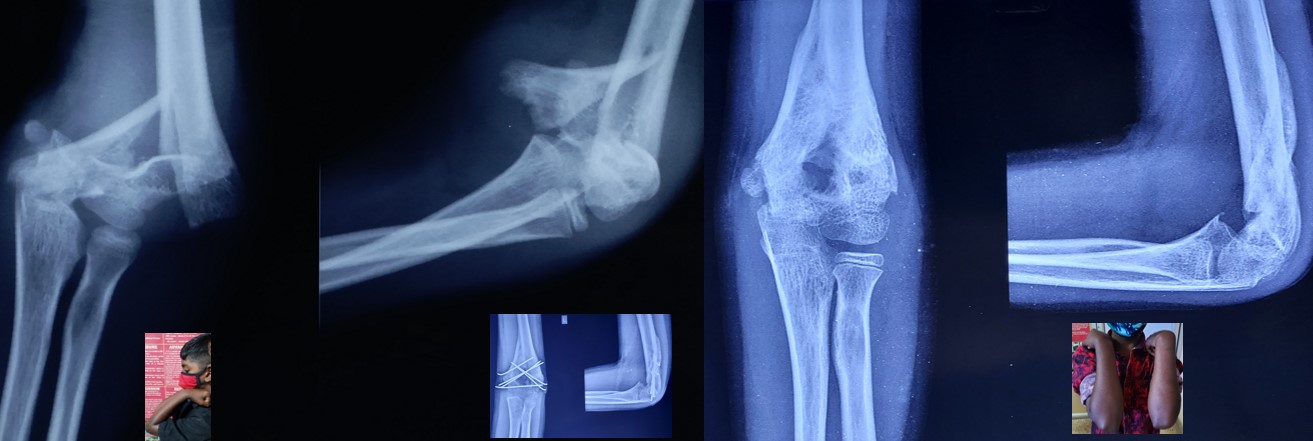

• It can be applied to any intraarticular fractures, distal end radius, elbow, ankle and foot.

·    97th Annual Meeting of Japanese Orthopaedic Association at Fukouka, Japan May-2024 presented CRPP of complicated  fractures Elbow in children.